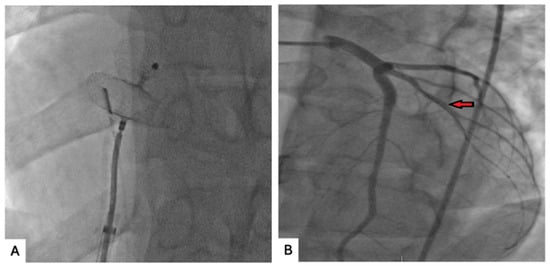

We describe the case of a 26-year-old man who presented with acute chest pain and was found to have single-vessel coronary occlusion most consistent with probable paradoxical embolism. Coronary angiography demonstrated complete occlusion of the ramus intermedius artery. Aspiration thrombectomy restored flow without

We describe the case of a 26-year-old man who presented with acute chest pain and was found to have single-vessel coronary occlusion most consistent with probable paradoxical embolism. Coronary angiography demonstrated complete occlusion of the ramus intermedius artery. Aspiration thrombectomy restored flow without stent implantation. Intravascular ultrasound showed no plaque rupture, atherosclerosis, or coronary dissection, supporting but not definitively confirming an embolic etiology. Transthoracic and transesophageal echocardiography subsequently identified a large patent foramen ovale with bidirectional shunting. Lower-extremity Doppler studies and an extensive hypercoagulable evaluation were negative. The patient later underwent successful percutaneous closure of the patent foramen ovale. This case highlights probable paradoxical coronary embolism as a rare cause of acute myocardial infarction in a young patient without significant atherosclerotic disease and underscores the value of multimodality imaging in supporting the diagnosis and guiding management.